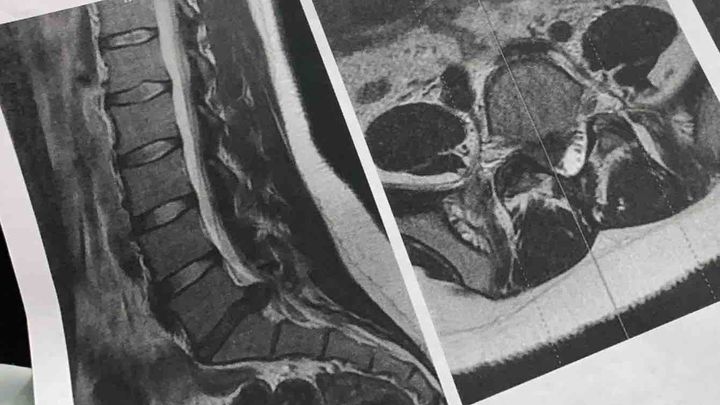

About a month and a half ago, I woke up one day not being able to move without being in excruciating pain. I ended up going to the ER and getting a MRI done.

I have a pretty bad herniated disc (my L5-S1 disc) that's been putting a huge amount of pressure on the nerve that runs down my leg & forcing stenosis. I'm only 20 years old.